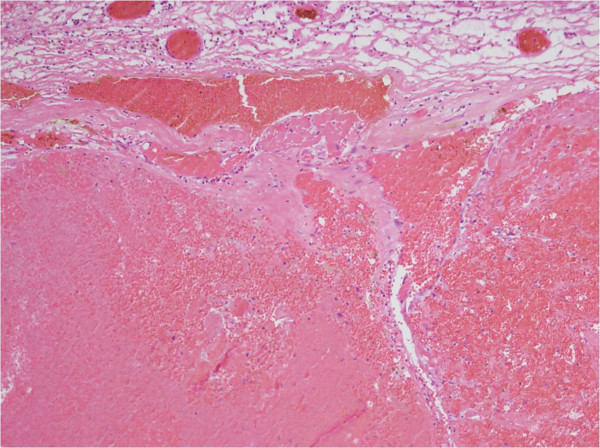

圖4:海綿狀血管瘤的病理表現(xiàn)。顯微照片顯示一個由不規(guī)則擴(kuò)張的通道組成的充滿血液的病變和圍繞該病變的輕微纖維化的包膜